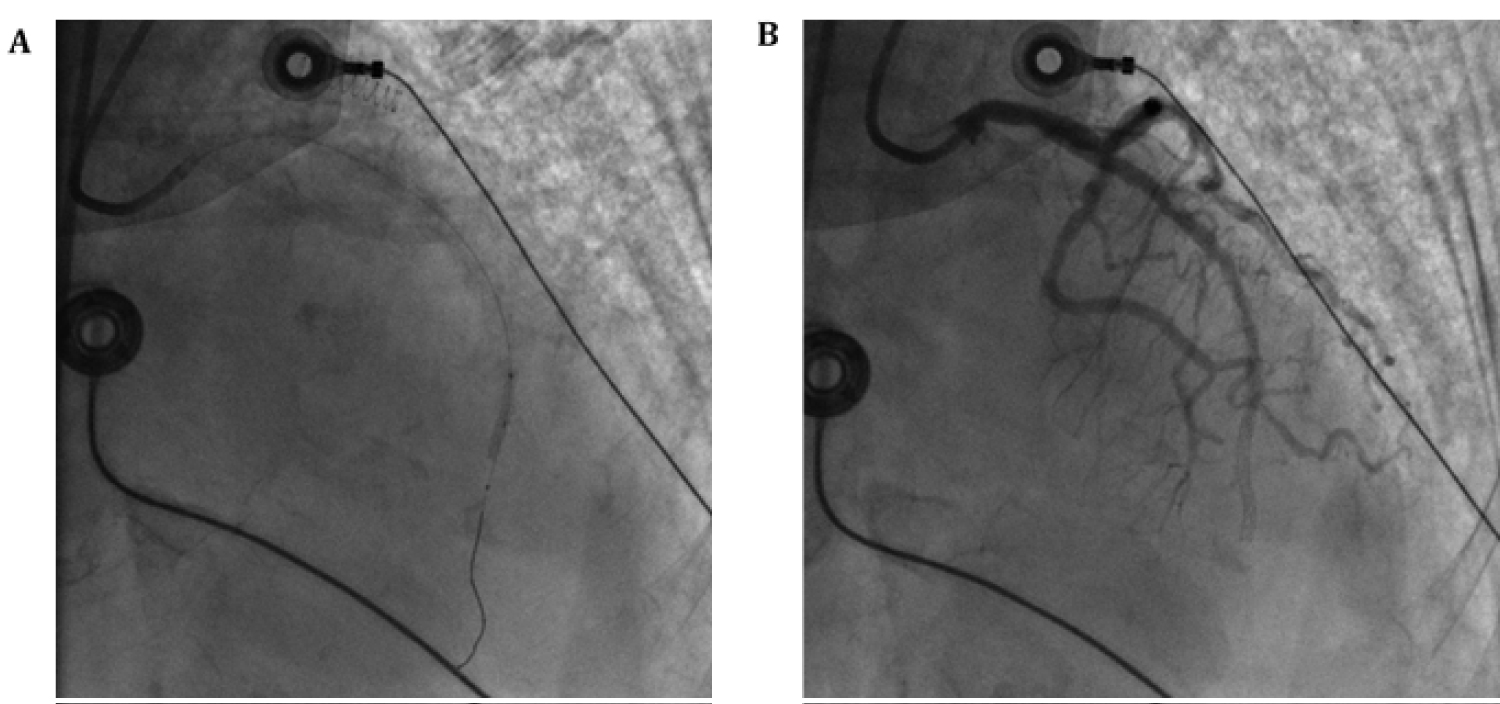

Cardiac catheterization showed 100% distal LAD lesion (Figure 6 and Video 4). Thrombectomy and PCI of the LAD lesion was performed with balloon angioplasty and stent placement but distal flow could not be achieved (Figure 7, Video 5 and Video 6). TTE post procedure showed mild segmental left ventricular systolic dysfunction with hypokinesis of the apex with an ejection fraction of 45% (Figure 8). She was transferred to the intensive care unit for further care.

Figure 7: (A) Coronary angiography of PCI; (B) Coronary angiography with continued poor distal flow after thrombectomy and PCI. View Figure 7